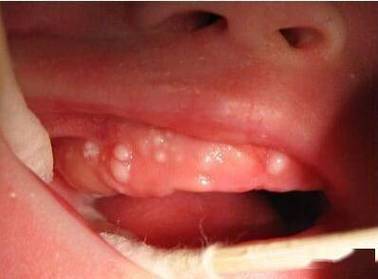

宝宝口腔内红色血点咋回事?

看到宝宝口腔内有红色血点,家长肯定会很担心,别慌,这其实是一个比较常见的现象,原因多种多样,有些是正常的生理现象,有些则需要引起注意。

下面我为您详细分析一下可能的原因、家庭观察要点以及何时需要就医。

可能的原因分析

最常见且通常无害的原因:创伤

- 吸吮/咬伤:宝宝在吃奶(母乳或奶瓶)、吃辅食或啃咬玩具时,不慎摩擦或咬伤了口腔内的娇嫩黏膜(如颊内侧、牙龈、上颚),导致毛细血管破裂出血,形成小血点。

- 擦伤:使用硬质勺子、安抚奶嘴或手指探入宝宝口腔过深,也可能划伤黏膜。

- 特征:血点通常出现在受力或摩擦的部位,形状不规则,周围黏膜可能有些发红,宝宝通常没有其他不适表现。

与出牙相关的因素

- 牙龈摩擦:长牙时,牙龈会肿胀、发痒,宝宝可能会用手指、玩具或衣服去摩擦牙龈,导致牙龈表面轻微出血,形成小红点。

- 特征:血点集中在正在萌牙的牙龈区域,宝宝可能会伴有流口水、烦躁、爱咬东西等出牙期症状。